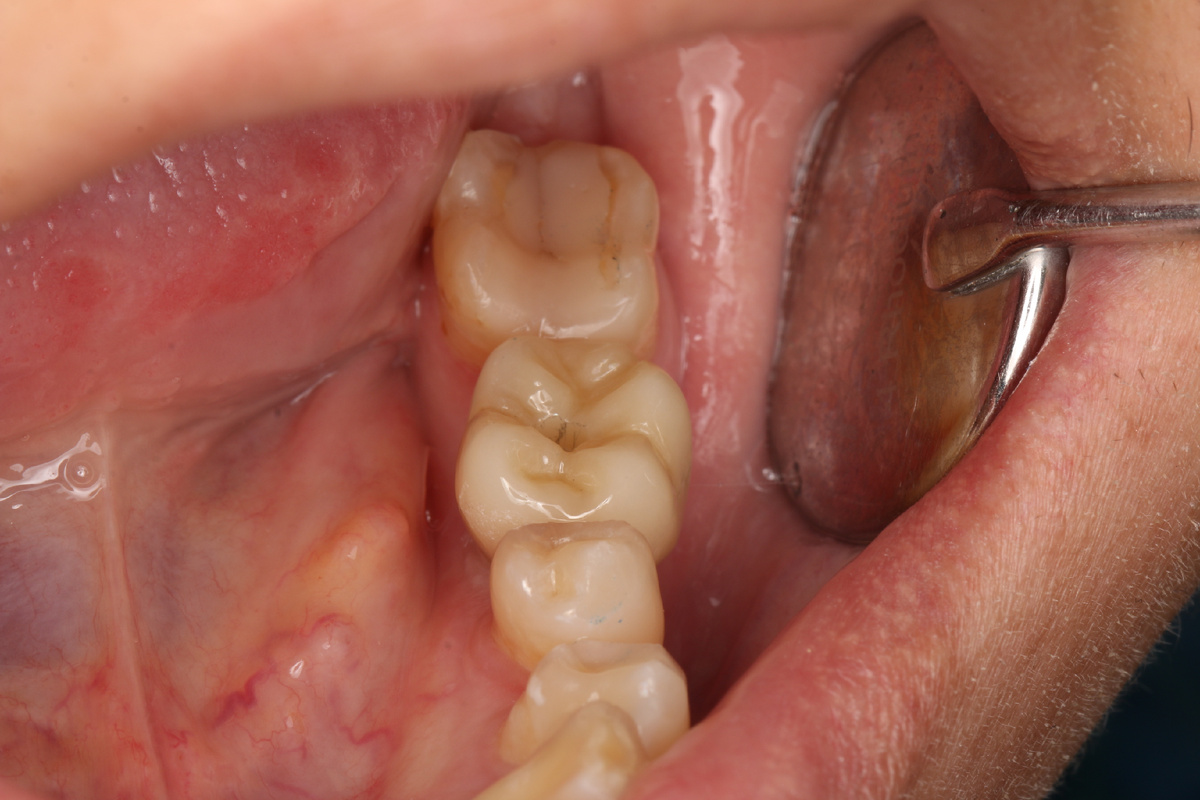

Зуботехнической лабораторией была изготовлена циркониевая коронка (из диоксида циркония). Однако в процессе внутриротовой примерки коронки я столкнулся с непредвиденной сложностью. Проблема видна сразу: коронка занимает крайне неправильное положение в зубном ряду. Это приводит к ряду серьезных осложнений: Данная работа подлежит переделке у зубного техника. В следующей публикации я представлю финальный результат лечения.

Проблема видна сразу: коронка занимает крайне неправильное положение в зубном ряду. Это приводит к ряду серьезных осложнений:

1. Отсутствие адекватного контактного пункта с соседними зубами. Из-за этого в промежутке будет постоянно застревать пища и скапливаться налет, что в будущем приведет к проблемам с имплантатом и будет вызывать у пациента постоянный дискомфорт.

2. Нарушение окклюзии (смыкания) коронки с антагонистами на верхней челюсти. Это приведет к перегрузке как зубов-антагонистов, так и самого имплантата.

3. Травма щеки из-за чрезмерно выпуклого бугра коронки, что будет вызывать у пациента постоянное прикусывание слизистой.

4. Выраженный эстетический дефект.

Данная работа подлежит переделке у зубного техника. В следующей публикации я представлю финальный результат лечения.